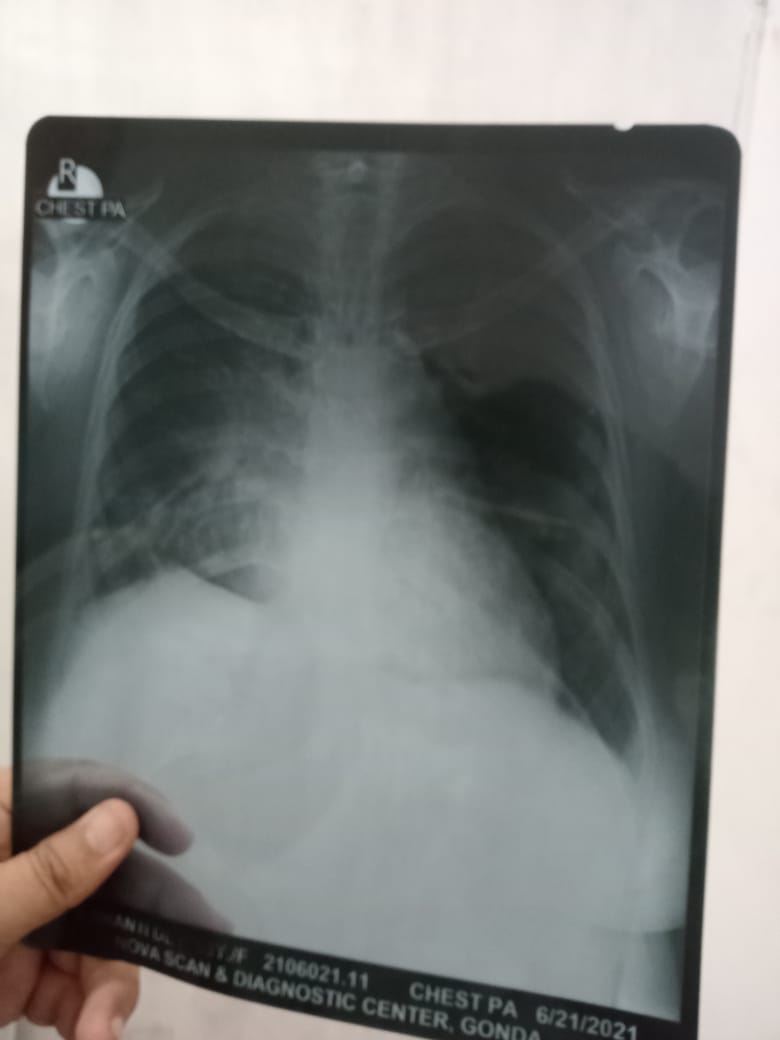

Complain of productive cough and breathlessness since 1 year …sphutum AFB negative…spo2 73.bp 120 / 80…took all type of asthamatic drug.kindly suggest treatment .